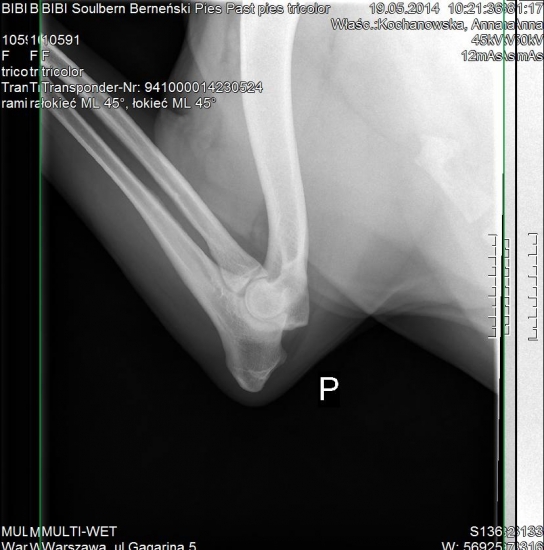

A ja mam kolejny powód do zadowolenia z moich Soulberniatek, w dniu dzisiejszym Bibi Soulbern przeszła pozytywnie, komplet prześwietleń pod kątem dysplazji stawów biodrowych, łokciowych i OCD stawów barkowych .

Bibi jest wolna od dysplazji z wynikiem HD A, ED 0/0, OCD neg. :-D :radocha2:

Łokiec lewy ED 0

obrazek

Obrazek został zmniejszony.